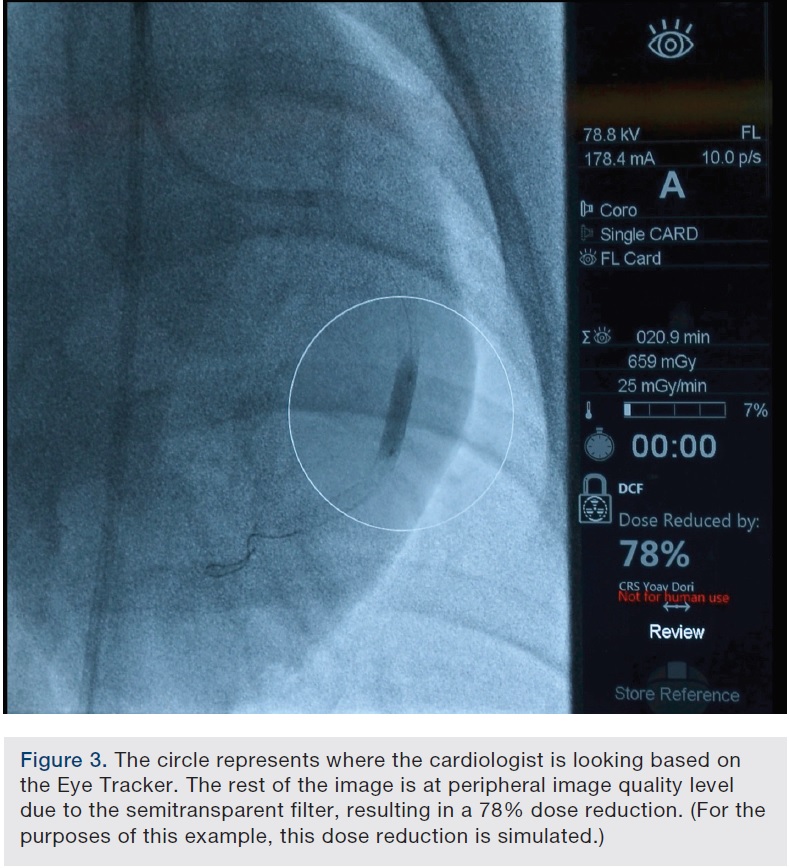

The basic principle capitalizes on how our visual system is designed. Only 5% of our field-of-view is clear; the rest is in our periphery. Yet we use the same amount of x-ray on the entire image, even though we can’t see it all at once. During an interventional procedure, although we want to know our surroundings, 90% of the time during fluoroscopy, we are focused specifically on the blockage itself. We are either passing wires, putting a stent or putting a balloon, or doing atherectomy, but essentially we are focused on a rather limited part of the screen. What if we could track where we were looking and focus the x-ray beam only where it is needed? That is the trick of this technology. It is able to track our eyes to determine where we are looking. It then moves, in real time, a semi-transparent filter that is above the tube in order to deliver perfect resolution where we need it, while delivering less radiation where we don’t need it — the part of the image that we aren’t looking at and that is in our peripheral vision. The end result is a 75% radiation dose reduction. For example, if the tip of the catheter is moving and I notice it in my peripheral vision, I will move my gaze to the catheter. The eye tracker will adjust its on-the-fly transparent filters to provide perfect resolution wherever I am looking, while keeping the rest of the image at a peripheral level image quality.

We conducted a study1 to quantify the dose reduction with the use of the eye tracker system. We performed coronary angioplasty and stenting in animals, comparing dose with and without the use of the eye tracker system. The procedures included wire passage and all the various steps. The eye tracking dose reduction technology demonstrated a 75% reduction in the radiation exposure measures. There were multiple measurements, because essentially this was a radiation physics study, not a clinical study. A special radiation physicist provided various detectors in multiple areas and all showed a significant level of reduction throughout the procedures. At the same time, we were able to perform the procedure very easily, without noticeable delays as we were looking at various parts of the screen.